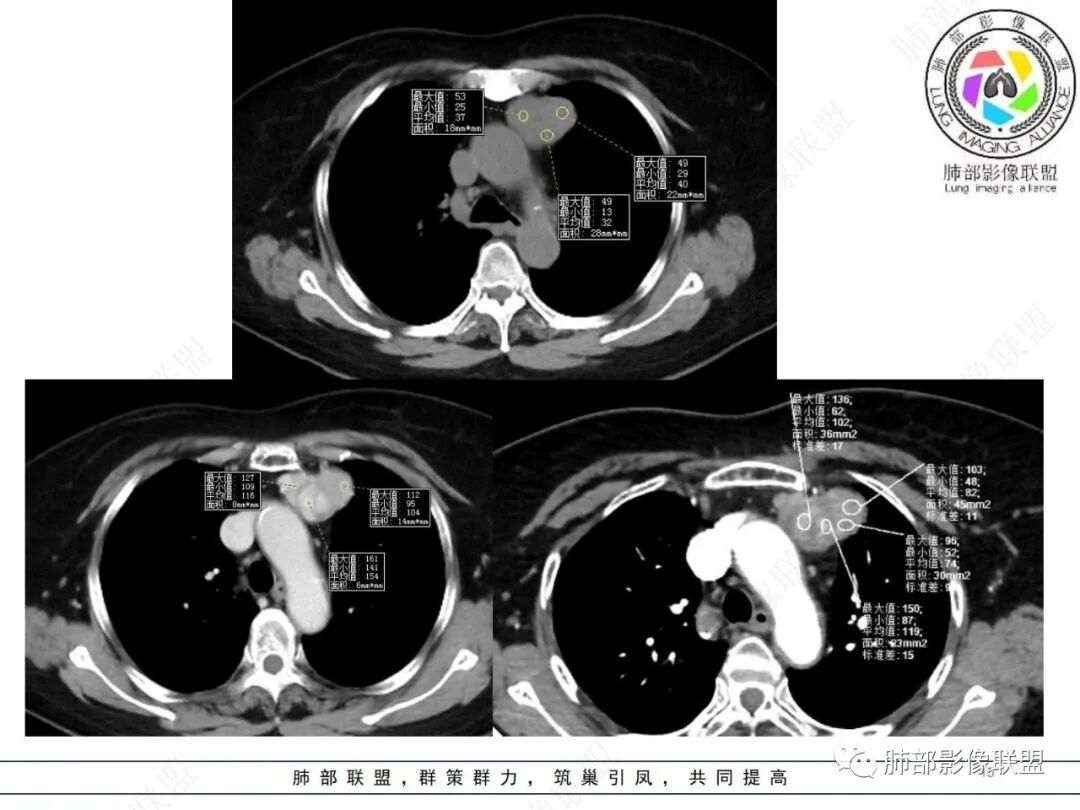

平扫密度较均匀,增强渐进性不均匀强化,内见低密度纤维分隔。未见肿大淋巴结。未见胸腔积液。

肿块边界清楚,低密度纤维间隔,未见侵犯转移及增大淋巴结,多见于胸腺瘤AB型

—强化程度及强化方式不支持常见的血管瘤及巨淋巴结增生症(CD)。

—患者血压高,应当排除副节瘤可能。病灶未见坏死区,且发生于纵隔的嗜铬性副节瘤罕见。